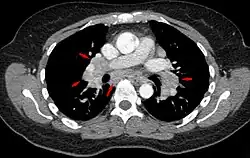

Sarkoidose in der Computertomographie: Querschnitt durch den Thorax im Bereich der Aufzweigungen der Bronchien (der Hili) mit vielen vergrößerten Lymphknoten (Pfeile)